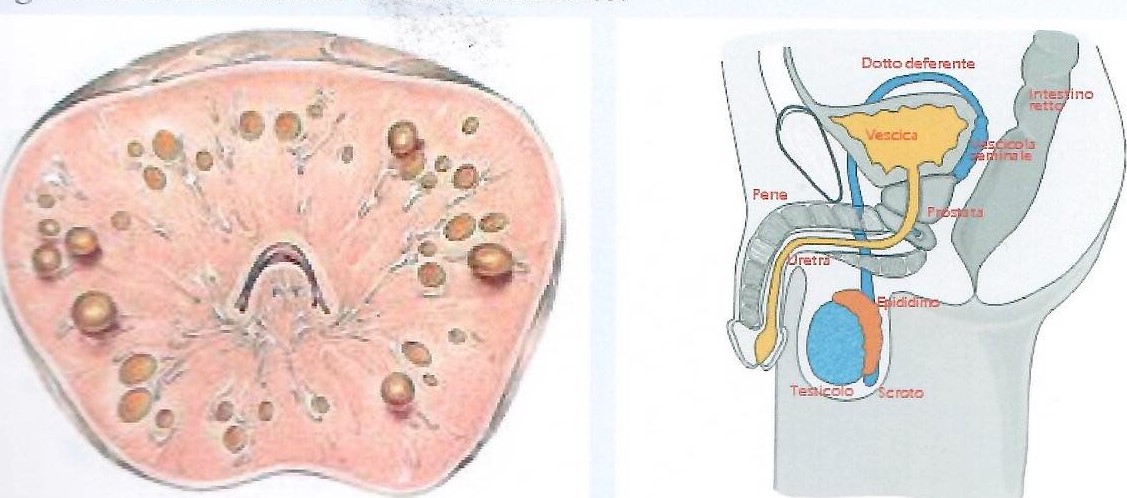

La prostata è un organo impari, mediano, della grossolana forma di una castagna posta sotto la vescica che circonda a "manicotto" l'uretra e che, per motivi ancora oggi ignoti, dopo i cinquant'anni subisce modificazioni cominciando a dare disturbi nell'urinare in 1 uomo su 5. In stretto rapporto tra prostata e vescica, si trovano le vescichette seminali. Tali organi, insieme ai testicoli ed alla prostata, concorrono a produrre il liquido seminale che grazie ai dotti deferenti verrà convogliato nel canale uretrale (uretra) ed eliminato all'esterno. A volte ad infiammazioni prostatiche si associano anche quelle vescicolari (prostato-vesciculiti).

La prostata è un organo formato da ghiandole che contribuiscono alla produzione di fluido spermatico necessario per l'eiaculazione e per il mantenimento della motilità e vitalità degli spermatozoi, che vengono prodotti a livello del testicolo e convogliati all'uretra tramite il dotto deferente.

Sezione di prostata Anatomia della pelvi